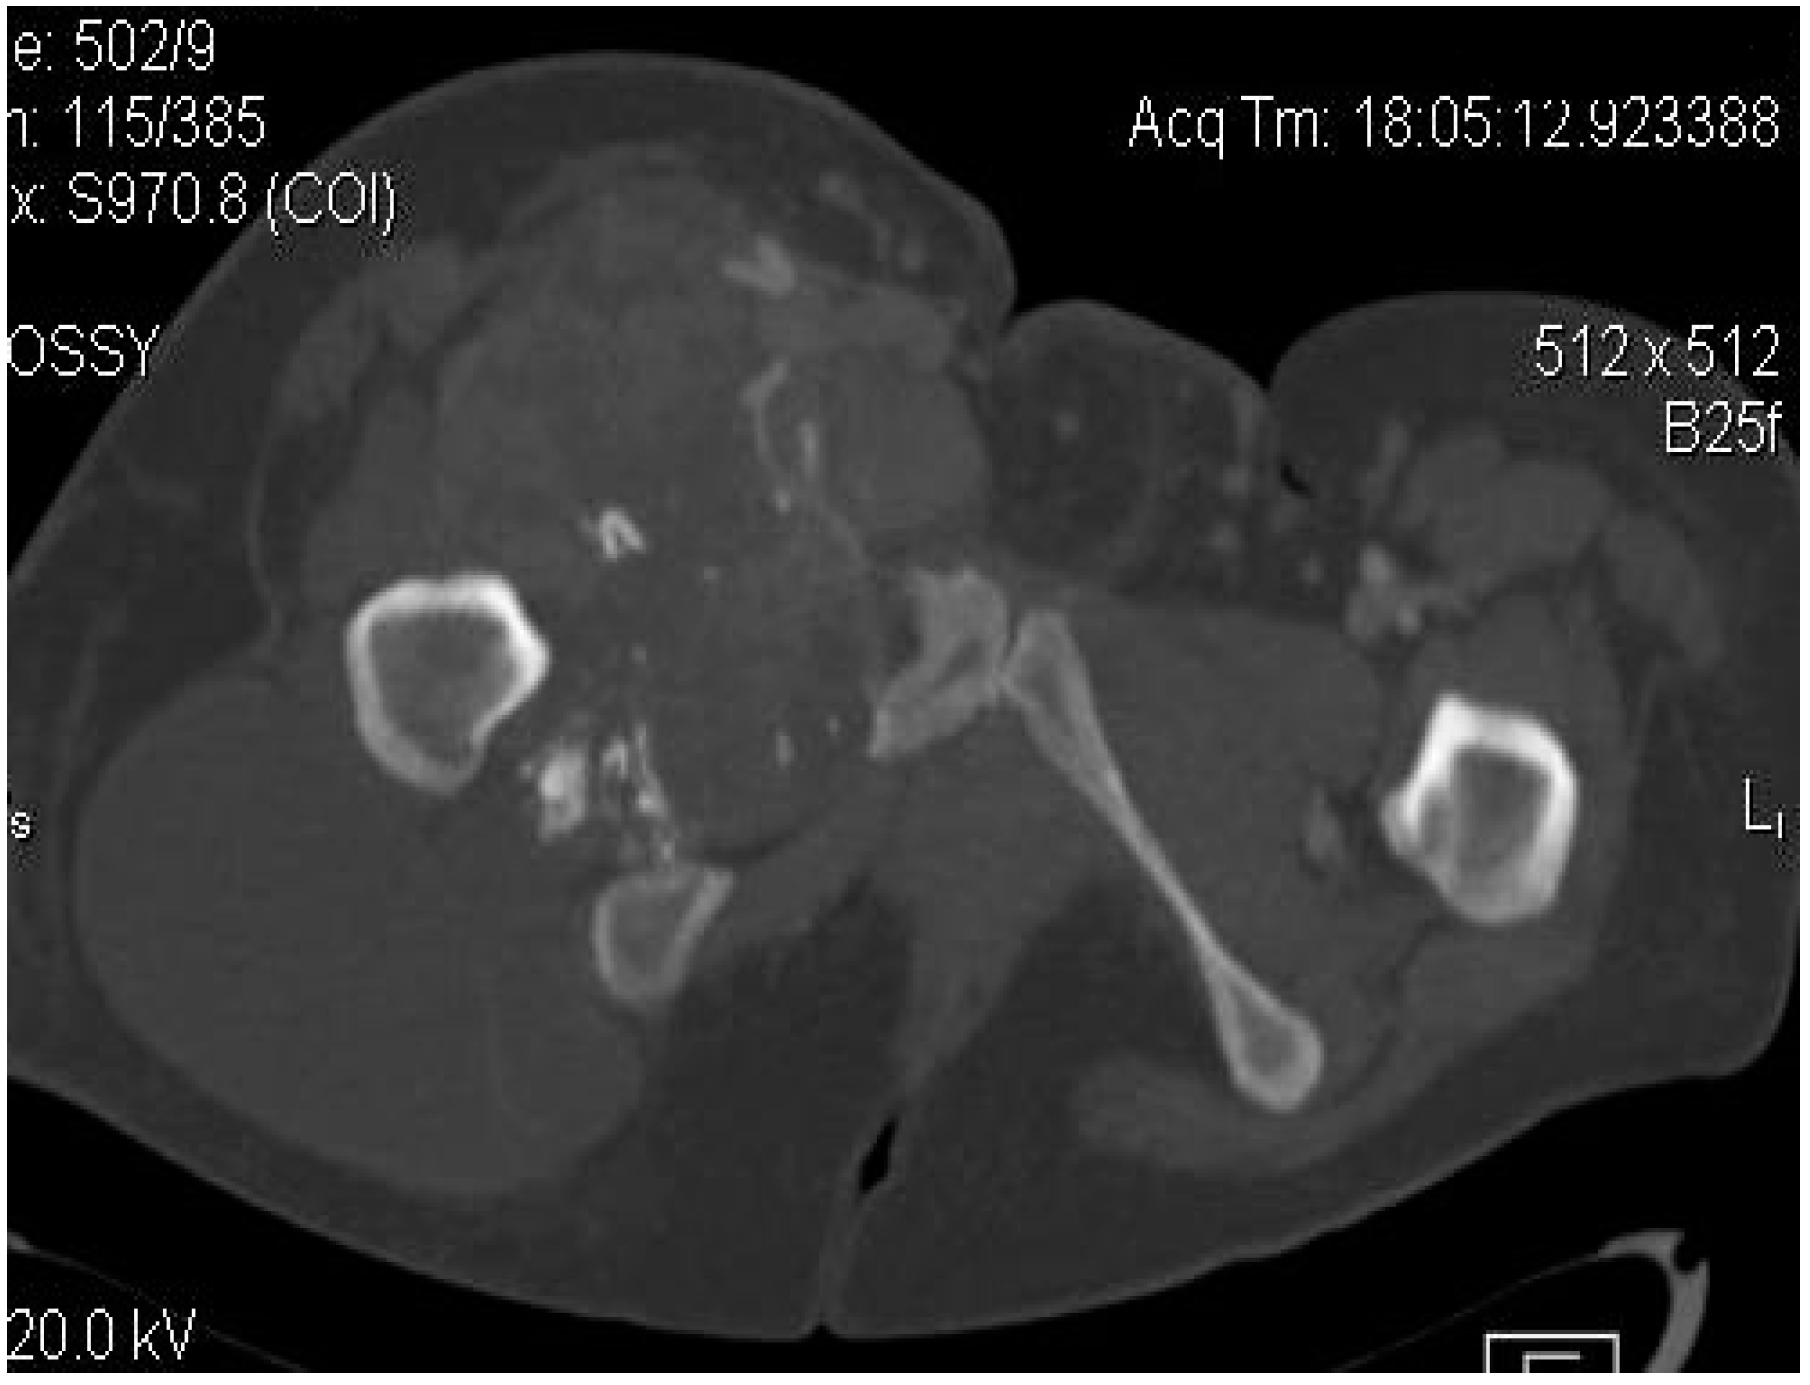

2.2. Imaging Examinations